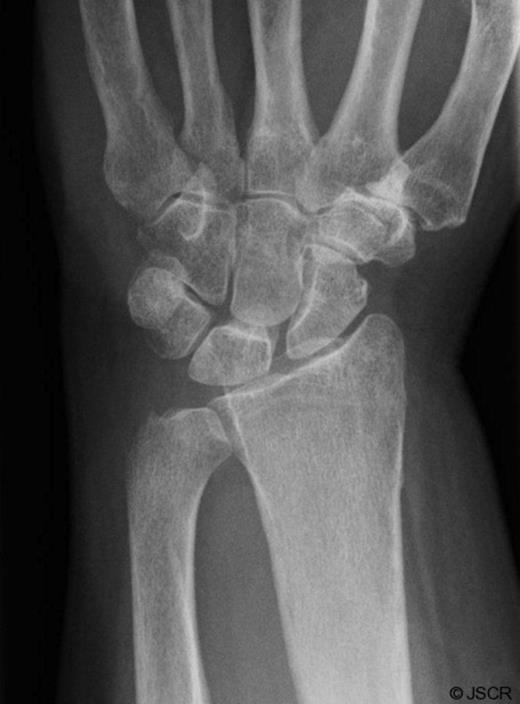

She was subsequently referred to the hand clinic. X ray this time showed destruction of the ulnar styloid consistent with a bony infection (Figure 2). MRI showed destruction localised around the ulnar head with oedematous changes extending up the shaft of the ulna (Figure 3).

AP Xray of the wrist showing destruction of the ulnar styloid consistent with a bony infection. Soft tissue swelling can also be noted over the dorsum of the wrist